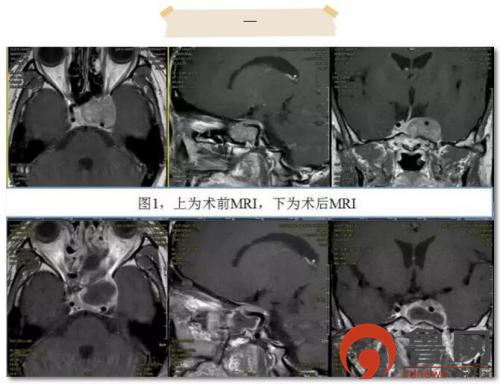

患者1为44岁中年女性,因“经鼻蝶垂体瘤术后16个月,头部胀痛半年”入院。术前鞍区MRI显示垂体瘤复发并侵袭左侧海绵窦,左侧颈内动脉完全被肿瘤包绕。手术的主要难点为如何切除海绵窦内的肿瘤。海绵窦是侵袭性垂体瘤最常见的侵袭部位,由于海绵窦内神经血管结构复杂,手术显露及切除难度增大,术后并发症增多,历来为手术禁区。王志刚教授术前组织科内多次进行讨论,最终形成意见,可采取两种手术方案:一是选择开颅手术,采取Dolenc入路,切开海绵窦顶壁及外侧壁,显微镜下切除肿瘤;二是选择经蝶微创手术,采取扩大蝶鞍的翼腭窝入路,切开海绵窦底壁及外侧壁,内镜下切除肿瘤。最终患者及家属决定行经蝶微创手术。术中开放后组筛窦、蝶窦、上颌窦后壁,显露翼腭窝,最终充分暴露鞍底及左侧海绵窦。当打开海绵窦的底壁及外侧壁后,静脉血涌出,这时不仅要切除肿瘤,还要在“血泊”中仔细辨别并保护海绵窦内走形的颈内动脉、动眼神经、滑车神经等,手术难度可想而知,恰如刀尖上跳舞。为保证安全,最终仅颈内动脉后方的一薄层肿瘤未勉强切除(图1),术中出血仅约200ml,术后患者未出现任何神经功能的缺失。脑脊液鼻漏经腰大池引流10日后完全缓解,患者顺利出院。